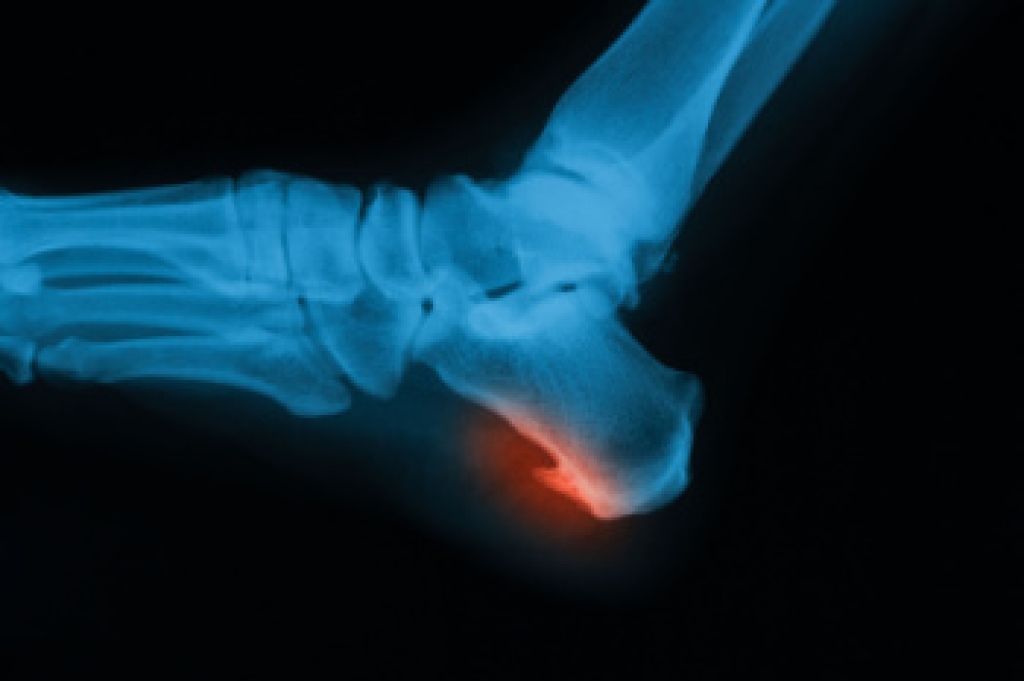

- Stress fractures can occur from overtraining, lack of calcium, or even your running style.